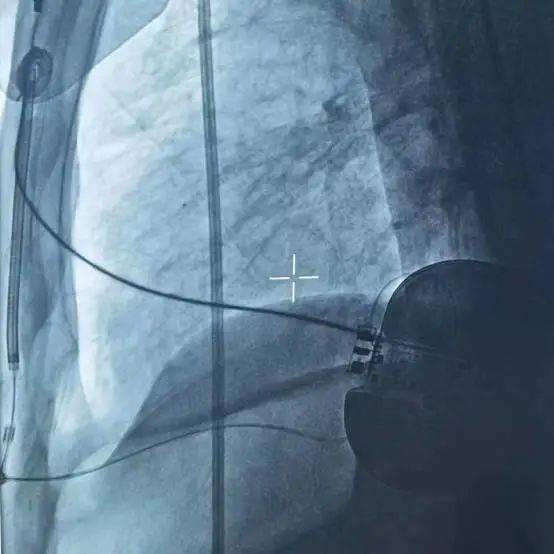

(术后影像)

手术在全身麻醉下进行,常规消毒、铺巾,取左腋中线平等第5-6肋为预定点,切开一长约5cm切口,逐层分离至深筋膜,分离囊袋至背阔肌与前锯肌之间。再于胸骨左缘1cm为预定点,切开一长约3cm切口,逐层分离至深筋膜层,预埋两根缝合线,用引导针,于切口间建立隧道,后引导除颤电极于皮下,固定除颤电极。于胸骨柄上缘(距下切口14cm处)为预定点,切开一长约2cm切口,逐层分离至深筋膜层,用导引针导引除颤电极于深筋膜层至上切口位置,固定电极头端,连接脉冲发生器(S-ICD 209),固定脉冲发生器于深筋膜层,排除空气后关闭皮下组织。进行除颤阈值测试,采用50HZ,200MA交流电方式进行诱颤,S-ICD正确识别,经首次65J除颤成功,除颤阻抗74Ω。缝合皮肤,术区纱布覆盖,包扎,弹力绷带加压包扎止血。手术圆满成功,耗时约1小时。送病人回病房。